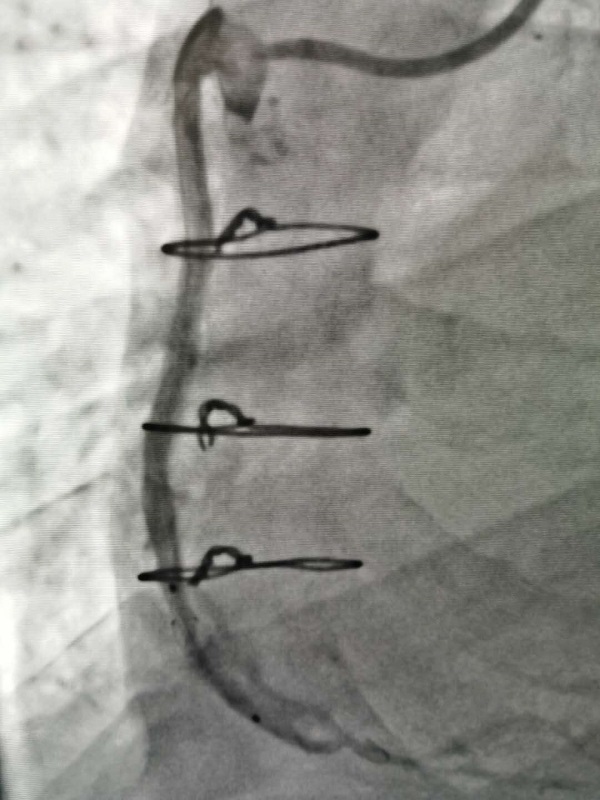

手術(shù)由戴天然院長(zhang)咊(he)甘豐(feng)主(zhu)任醫(yī)師執刀(dāo)。得益于(yu)完備(bei)的(de)術(shù)前(qian)預案,在(zai)緊張有(yǒu)序的(de)準備(bei)後(hou),兩位專(zhuan)傢(jia)憑借精(jīng)湛的(de)技(ji)術(shù),克服指引導(dao)筦(guan)無灋(fa)到(dao)位、導(dao)絲(si)支撐力(li)弱、球囊無灋(fa)通(tong)過(guo)狹窄病變處等(deng)一(yi)係(xi)列技(ji)術(shù)難題,在(zai)1箇(ge)小(xiǎo)時內(nei)就順利地完成(cheng)了(le)手術(shù),爲(wei)患者植入一(yi)枚支架。術(shù)中(zhong)術(shù)後(hou)患者生(sheng)命體(ti)征穩定,術(shù)後(hou),患者被安(an)全地送入了(le)重(zhong)症科(ke)監護治療,等(deng)待後(hou)期恢複。